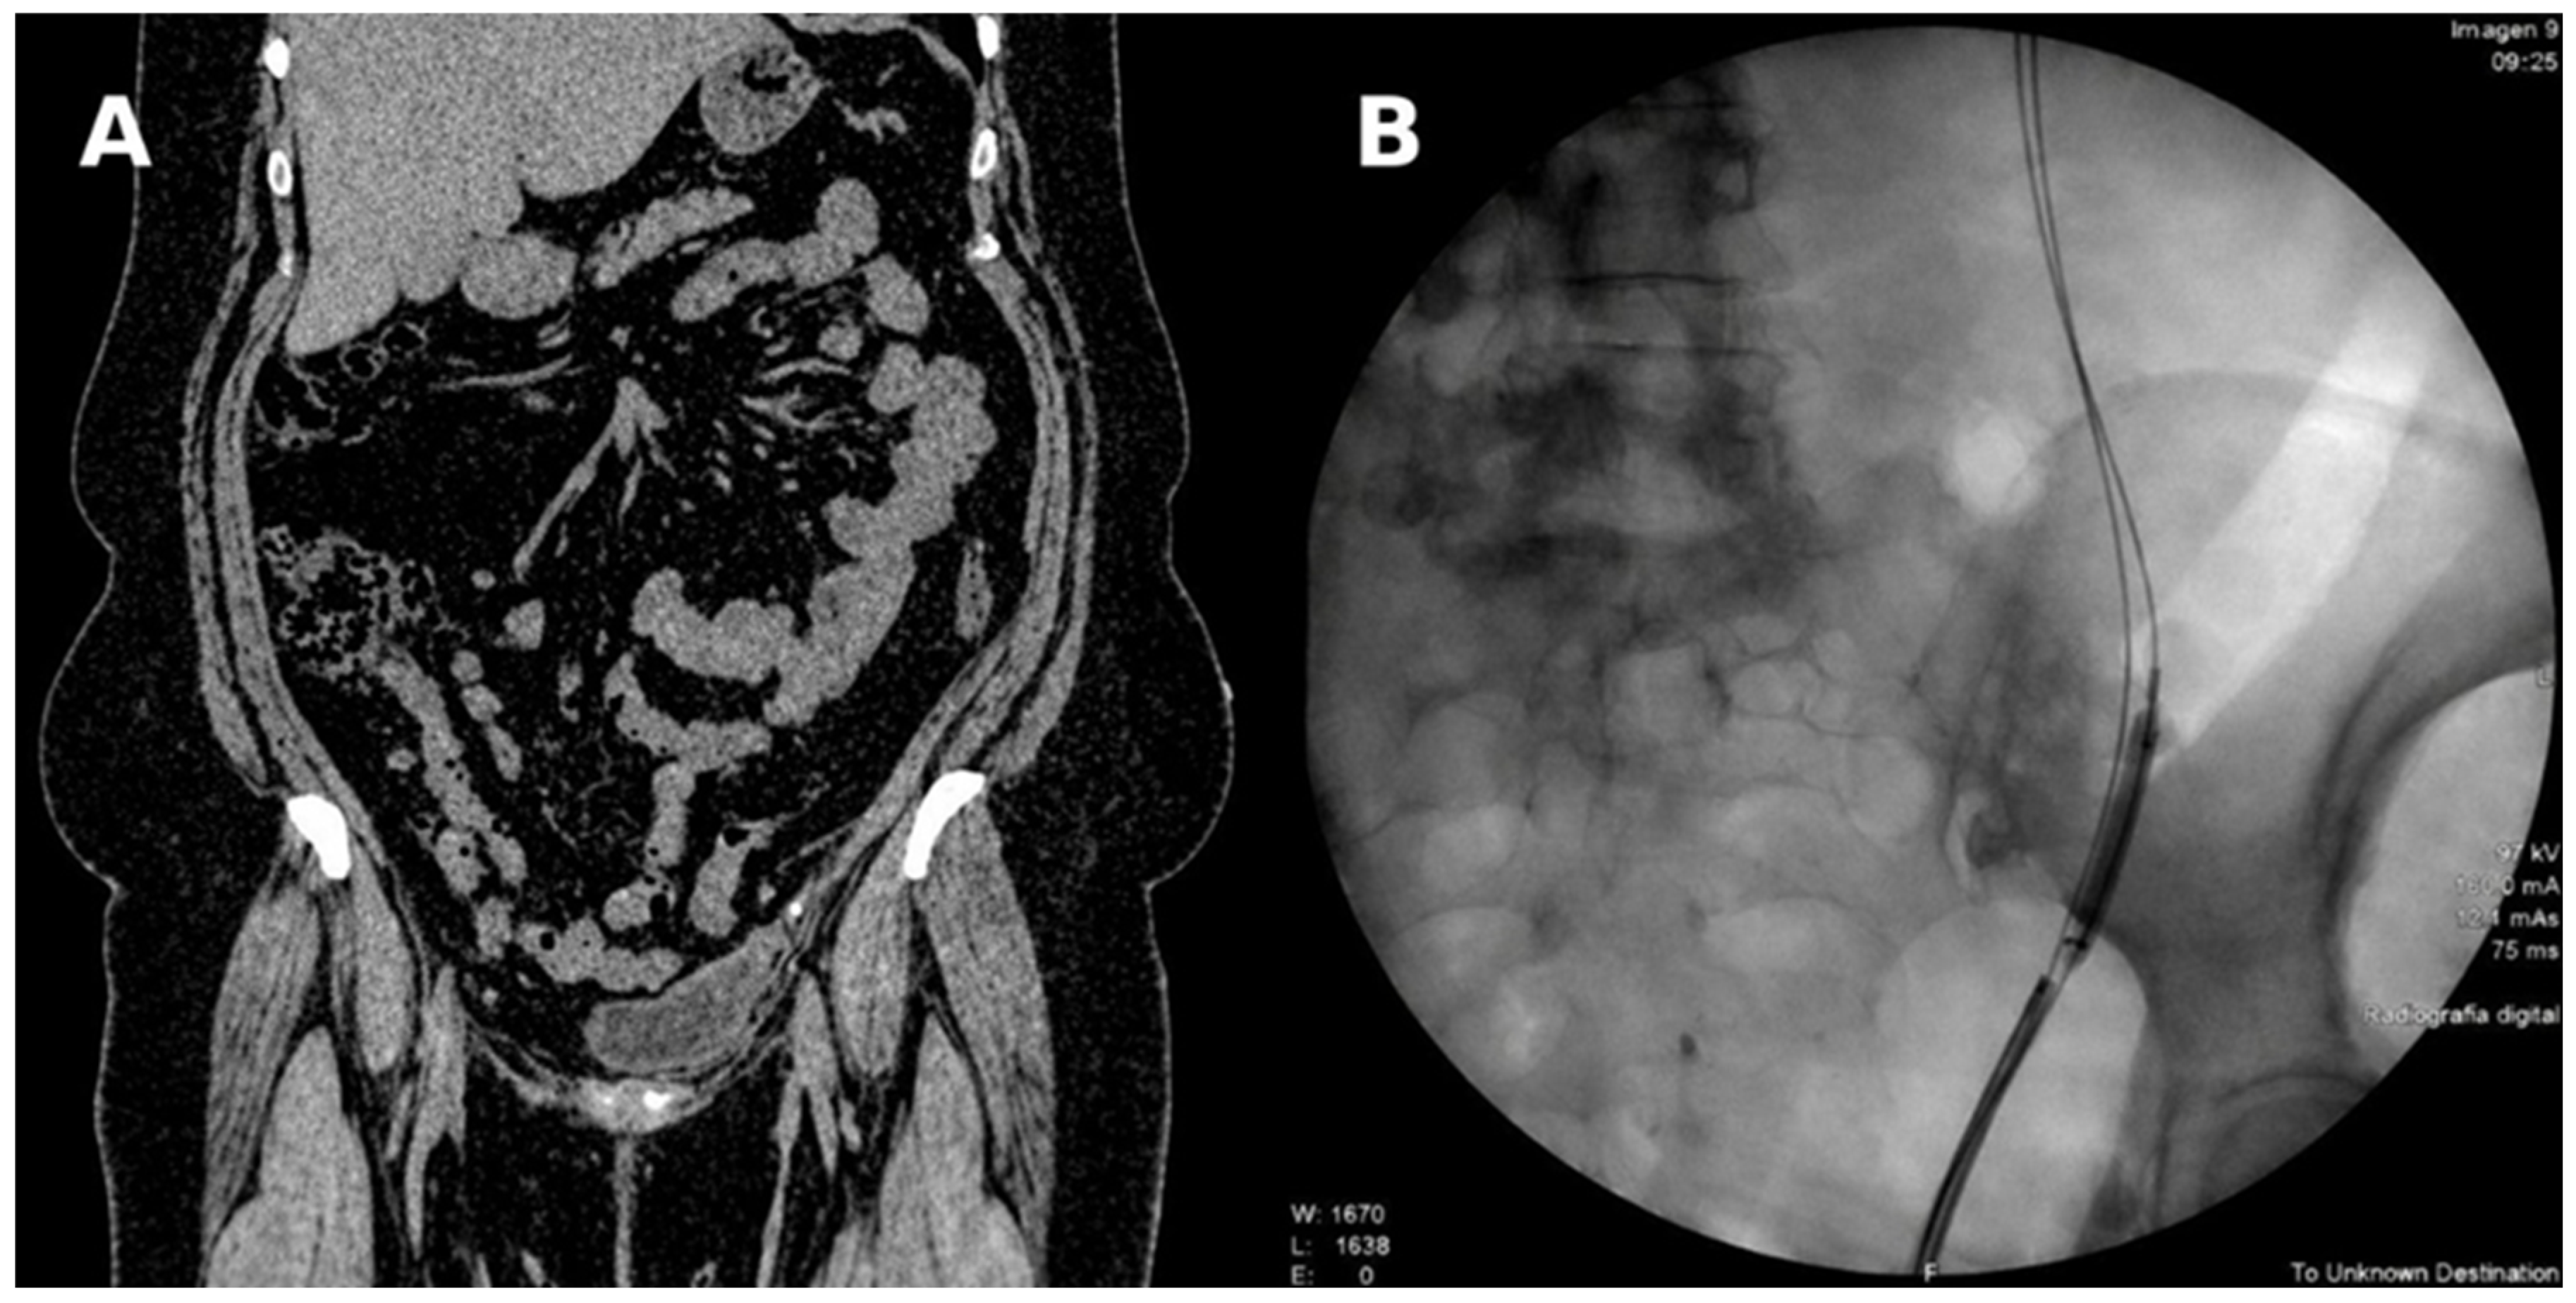

| Mar 2023 | Left renal colic → DJ stent placement | DJ stent (left) | CT: Grade IV hydronephrosis, distal ureteral stones | — |

| Oct 2024 | Combined pyelography | Nephrostomy | Distal stricture 2.5 cm | — |

| Mar 2025 | Reimplantation + psoas hitch | DJ + nephrostomy | — | — |